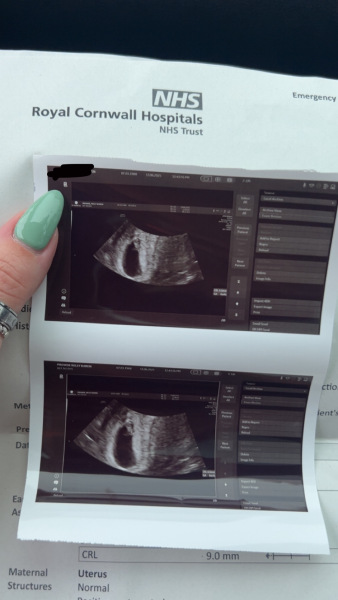

Kels21 · 13/06/2025 16:36

There’s only a beautiful little baby in there with a strong heartbeat 🥹🤍

Hcg levels at 6ish weeks